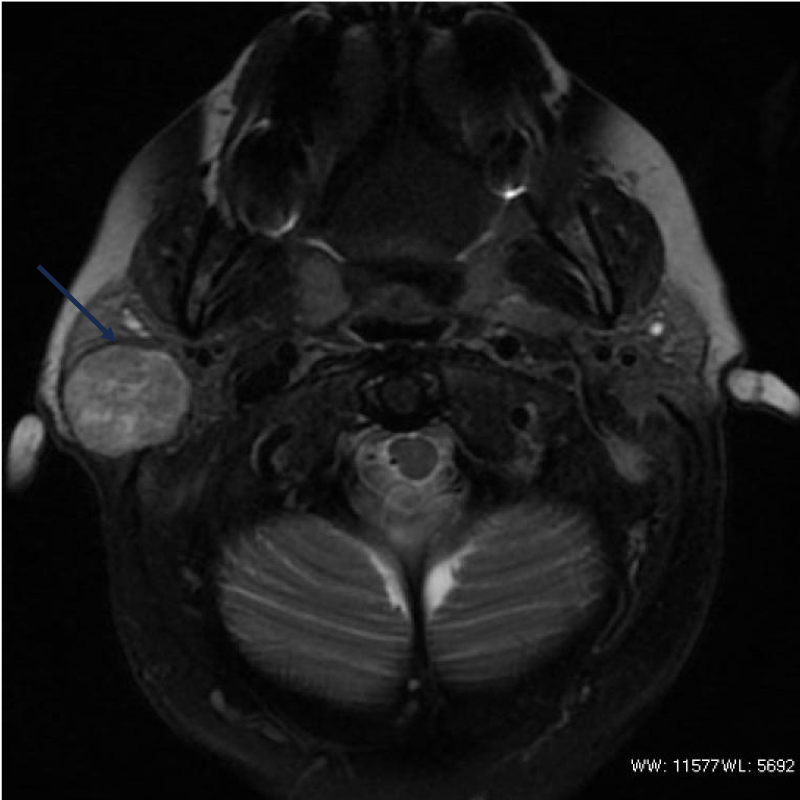

- les tumeurs, le plus souvent bénignes, mais parfois cancéreuses, principalement au niveau de la glande parotide, située latéralement au niveau de la joue et en avant de l’oreille ; mais aussi au niveau des glandes salivaires accessoires.

La chirurgie des tumeurs des glandes salivaires est variable selon la localisation et le type tumoral. Un bilan d’imagerie préalable est nécessaire. Une exérèse complète ou partielle de la glande comprenant la tumeur est souvent indiquée. Une chirurgie ganglionnaire peut être aussi recommandée en cas de tumeur à potentiel malin.

Avant l’intervention chirurgicale, vous devez consulter votre chirurgien muni d’un bilan d’imagerie, si tel n’est pas le cas, il sera prescrit lors de la première consultation (panoramique dentaire et échographie cervicale si suspicion de lithiase/ TDM cervico-faciale et IRM parotidienne si suspicion de tumeur). Votre chirurgien décidera en fonction de la pathologie suspectée et du bilan d’imagerie, l’indication d’exérèse et son caractère plus ou moins urgent. Une consultation pré anesthésique est obligatoire en cas d’anesthésie générale ou de neuroleptanalgésie (anesthésie semi profonde sans intubation associée à une anesthésie locale).